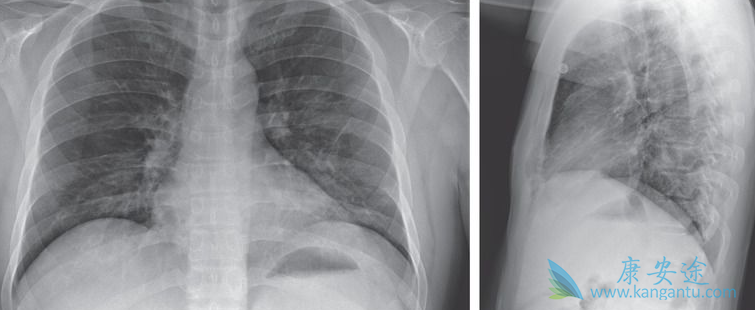

瑞德西韦(Remdesivir)三期临床试验到底是如何进行?临床试验分为两个试验进行。一个针对重症,一个针对轻症和中症。据披露信息,截至2月13日上午,试验只进行了重症,正在招募患者,共计452人。不知是否存在先实施临床试验,后面再在系统中补充更新的情况。

多中心的临床测试:也就是不止在金银潭医院进行。具体有多少家医院没有披露。金银潭医院完成一半或者一半以上的试验。对试验组和对照组患者施用的药物,未披露除了施用瑞德西韦/安慰剂外,是否对患者有优化的标准医护。照理说重症患者,不可能只用瑞德西韦/安慰剂。

根据金银潭医院院长的说法,具体试验时,盲法投入的药更多一些,基本是2:1的比例,就是两个人给的瑞德西韦药,一个人是给的安慰剂。施药方法是在第1天给予200毫克瑞德西韦的负荷剂量后,随后每天静脉注射一次100毫克维持剂量,持续9天。不知道如果药物有效,24-48小时就起作用的话,是否继续给患者注射维持剂量到整十天。